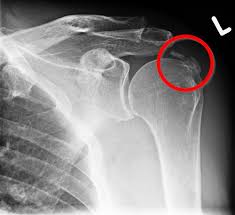

Der Verlauf der Kalkschulter variiert individuell man unterteil die Erkrankung in 4 Stadien. Eingriff dauert 20 Minuten danach ist der Kalk weg. Ob die KK Kosten übernimmt klärt sich morgen.

Die Operation einer Kalkschulter sei eine kurze unkomplizierte Sache sagt Karim Eid. Die Kalkschulter tritt bei vielen Menschen zwischen dem 30. Nicht bei jedem Patienten verläuft der Heilungsprozess gleich schnell auch wenn es. Ein schmerzarmes Initialstadium während dem es zu Umbauten im Gelenk kommt die Phase der Kalkeinlagerung in der bewegungsabhängige Schmerzen auftreten die Phase der Resorption in der die Schmerzen häufig am stärksten sind. Behandelt wird in der Regel zunächst konservativ also ohne Operation. 6 Wochen Schonung damit sich die Sehnen erholen können. Bei Behandlung durch Stoßwelle die wir regelmäßig vorziehen und mit nur wenigen Ausnahmen sehr erfolgreich finden. Man ist natürlich gehandicapt - ich sage es braucht ca. Eine halbe Stunde danach darf man den Arm sofort bewegen.